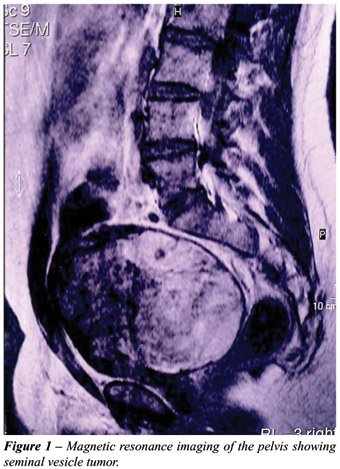

Pelvic magnetic resonance showed a 17 cm retrovesical mass (Figure-1) and a trans-rectal ultrasound guided biopsy revealed small round cells for which immunohistochemical findings suggested a primitive neuroectodermal tumor diagnosis. Two cycles of neo-adjuvant chemotherapy consisting of vincristine, cyclophosphamide, doxorubicin, ifosfamide and etoposide were performed, resulting in no radiological response.